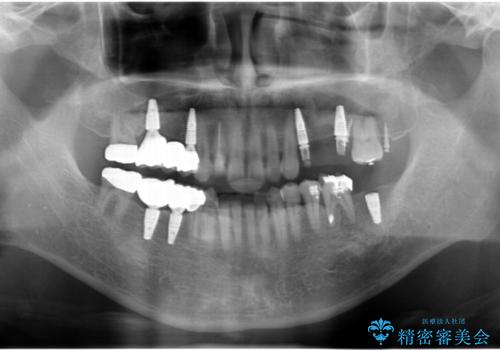

インプラント治療・セラミック治療を含む 全顎的虫歯治療

- 「 仕事が忙しく、虫歯を放置しすぎてしまった。この際全てきっちりと治したい。」と来院されました。

・歯の欠損

・虫歯

・深い虫歯

・欠損の放置による対合歯の挺出

・咬合平面の乱れ

・感染根管

以上のような問題を、徹底的な虫歯治療、歯周外科、インプラント治療、部分矯正治療、精密根管治療を用いてひとつずつ解決ししっかりと長期的に食事を楽しめるような口腔内環境の再構築を目指します。